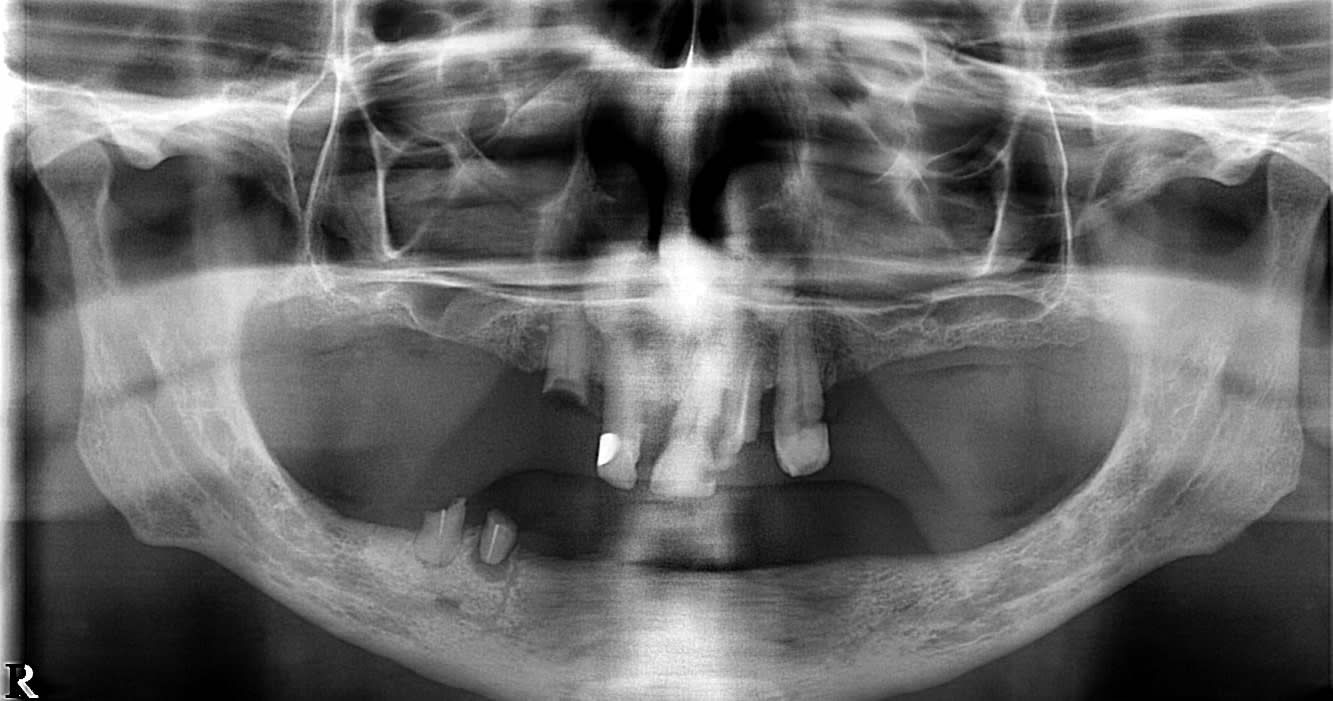

Bonjour, je ferai (ceci est tout à fait personnel) un complet haut, rebasée régulièrement avec une résine molle, que tu changes tous les 6 mois, ceci n'a un avantage d'avoir une très bonne rétention et aucune douleur, la pose d'implants me paraît très difficile sans chirurgie vue la pano ,et à la mandibule je ferai 2 attachements type LOCATOR qui ont une très bonne rétention et très facile d'entretien.